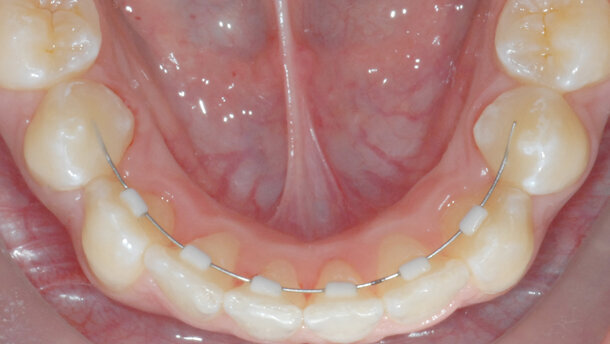

Si può iniziare da qui, andando indietro di qualche anno e leggendo il lavoro di John F. Shenck, The role of magnetic susceptibility in magnetic resonance imaging: MRI magnetic compatibility of the first and second kinds, pubblicato nel 1996 sulla rivista della American Association of Physicists in Medicine, che analizza la suscettibilità magnetica di alcuni materiali utilizzati in medicina e chirurgia, valutandone la compatibilità con la RMN (Fig. 1). Nella tabella originale viene evidenziato come la Zirconia (ZrO2) stia nella regione di compatibilità con la RMN. Questo significa che tale materiale, che è un metallo bianco, non crea fenomeni di magnetismo che possono interferire con il buon esito e accuratezza diagnostica di questo esame. Da un lavoro successivo, del 2006, pubblicato da T.M. J. Harris sul Journal of Orthodontics, dal titolo The benefits of aesthetic orthodontic brackets in patients requiring multiple MRI scanning, vengono evidenziati i benefici di utilizzare apparecchiature ortodontiche fisse estetiche in pazienti che, a causa di patologie interessanti il distretto testa e collo, devono sottoporsi routinariamente a RMN (compresa la rimozione temporanea degli archi in acciaio prima dell’esame), al fine di non incorrere in distorsioni, distacchi o movimenti dell’apparecchiatura stessa causati dai metalli tradizionali utilizzati, che possono risultare pericolosi, potendosi creare anche correnti elettriche e surriscaldamento dei tessuti, oltre ad artefatti di immagine, che possono inficiare l’esito dell’esame (Figg. 2a, 2b). In questo studio si raccomanda, inoltre, di controllare che i retainer fissi siano ben cementati prima della RMN, mentre viene evidenziato come gli archi in nichel titanio non siano da considerare ferromagnetici.

Partendo da queste considerazioni e analizzando la frequente richiesta da parte dei radiologi di rimuovere apparecchiature ortodontiche o contenzioni fisse in pazienti che per motivi accertati di salute (patologie come la sclerosi multipla) o in urgenza (per esempio in caso di traumi o incidenti) si devono sottoporre a RMN, è nata, dagli studi e dalle analisi del gruppo di lavoro diretto dal prof. Aldo Macchi, nell’ambito dell’attività di ricerca del Dipartimento di Scienze Chirurgiche e Morfologiche dell’Università dell’Insubria a Varese, una nuova famiglia di apparecchiature ortodontiche fisse costruite in Zirconia. La Zirconia è un metallo bianco e resistente con cui si possono costruire mediante fresatura con tecnologia CAD/CAM, non solo protesi ma, oggi, anche bracket per apparecchi ortodontici e sistemi di contenzione fissa (anche di colore customizzato), che non interferiscono con la risonanza magnetica nucleare e la cui estetica è un benefit aggiuntivo non primario.